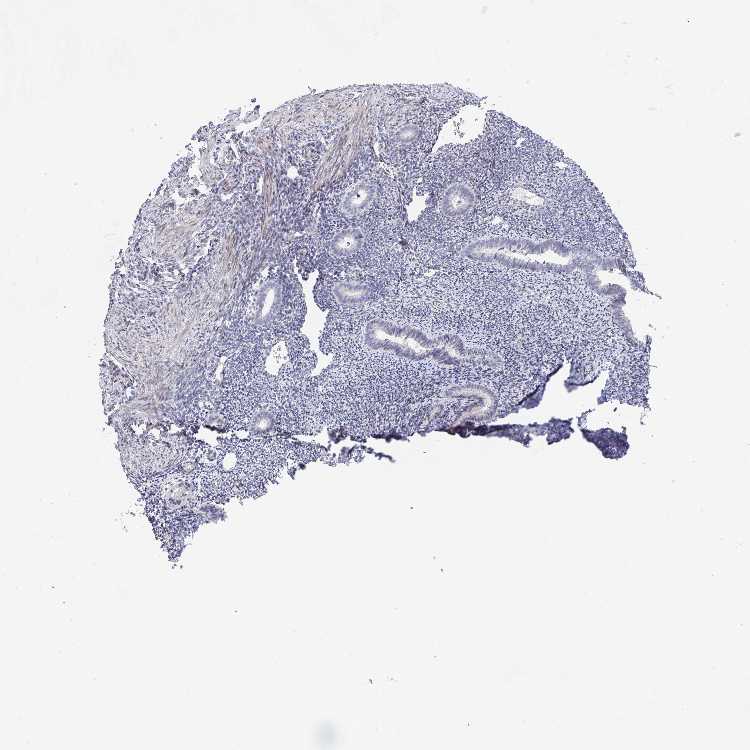

ENDOMETRIUM 1 - Antibody stainingi

Antibody staining in the annotated cell types in the current human tissue is reported as not detected, low, medium, or high, based on conventional immunohistochemistry profiling in selected tissues. This score is based on the combination of the staining intensity and fraction of stained cells.

Each image is clickable and will lead to virtual microscopy that enables deeper exploration of all samples and also displays staining intensity scores, fraction scores and subcellular localization as well as patient and tissue information for each sample.

Antibody HPA052936

Cells in endometrial stroma Not detected

Glandular cells Not detected

ENDOMETRIUM 2 - Antibody stainingi

Cells in endometrial stroma Low

Glandular cells Low